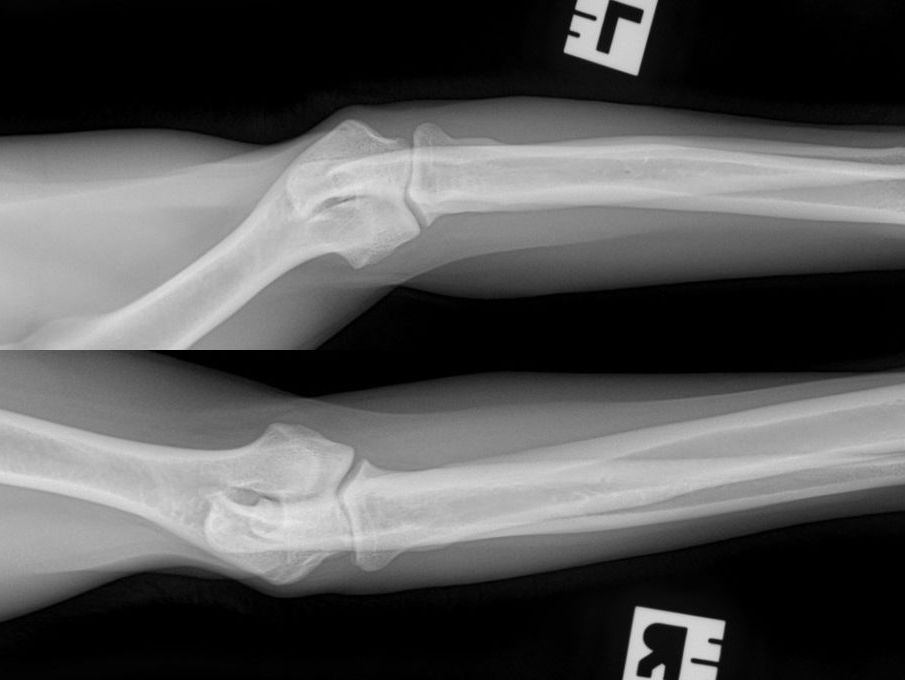

Hieronder foto's van Guus genomen met onze nieuwe DRgem rontgen. Beoordeeld met de hoogste score door de Raad van Beheer op Kynologisch gebied

Elleboogdysplasie (ED) onderzoek

Elleboogdysplasie is een ontwikkelingsstoornis van de ellebooggewrichten, met name het kraakbeen is aangetast. Deze aandoening kan erfelijk zijn, maar omgevingsfactoren spelen soms ook een rol. Er zijn honden die op jonge leeftijd al problemen ondervinden door ED, soms komt het pas op latere leeftijd tot uiting. Om te kunnen zien of uw hond ED heeft zijn röntgenfoto’s van de ellebogen nodig.

Voor een aantal rassen is een diagnose-onderzoek verplicht. Bij dit onderzoek dienen er per elleboog vier foto’s in vier verschillende richtingen gemaakt te worden (dus in totaal 8 foto’s). Deze rassen zijn: Labrador Retriever, Golden Retriever, Chesapeake Bay Retriever, Rottweiler, Berner Sennenhond, Duitse Herdershond, Bordeaux Dog.

Voor alle andere rassen volstaat een onderzoek met twee foto’s per elleboog. Meestal passen wij een lichte sedatie toe bij het maken van de officiële ED-foto’s. Dit is nodig om een kwalitatief goede foto te maken, welke aan de hoge eisen van de beoordelingscommissie moet voldoen. Uw hond moet op zijn of haar zijde en borst liggen, waarbij de elleboog in verschillende houdingen wordt gelegd.